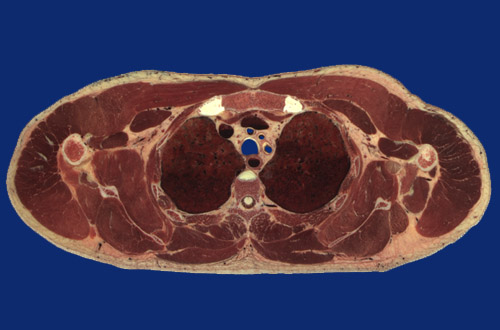

Identify the following regions in the image above: Pectoralis major - Pectoralis minor - Transversus thoracis - Coracobrachialis and short head of biceps - Deltoid - Humerus - Teres minor - Teres major - Long head of triceps - Lateral head of triceps - Infraspinatus - Subscapularis - Scapula - Sacrospinalis - Trapezius - Rhomboid major - Intercostal m. - Serratus anterior - Erector spinae m. group (Sacrospinalis) including iliocostalis, longissimus dorsi, spinalis dorsi - Transversospinalis m (semispinalis part) - Manubrium of sternum - Sternoclavicular joint cartilage - Left brachiocephalic vein - Right brachiocephalic vein - Brachiocephalic artery - Left common carotid artery - Left subclavian artery - Trachea - Esophagus - Vertebral body - Spinal cord - Right upper lobe - Left upper lobe